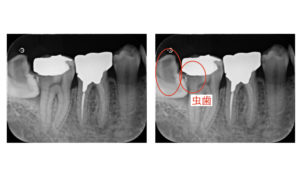

②手前の歯が虫歯になる

斜めになった親知らずと手前の歯との間は歯磨きをすることが難しく、虫歯になってしまうことがよくあります。

虫歯になった場合、親知らずを抜歯してから虫歯の治療をすることとなります。

この場合虫歯を削り取り詰め物をすることで治療完了です。

ただしこの部分の虫歯治療は非常に大変で予後もあまり良くありません。

また、治療手段もかなり限られてきます。

大きな虫歯にってしまった場合は歯の中の神経まで取り除く必要が生じてしまいます。

親知らずがなければ手前の歯の神経は残せたかもしれないので、この状態になるまでに抜歯をするべきでしょう。